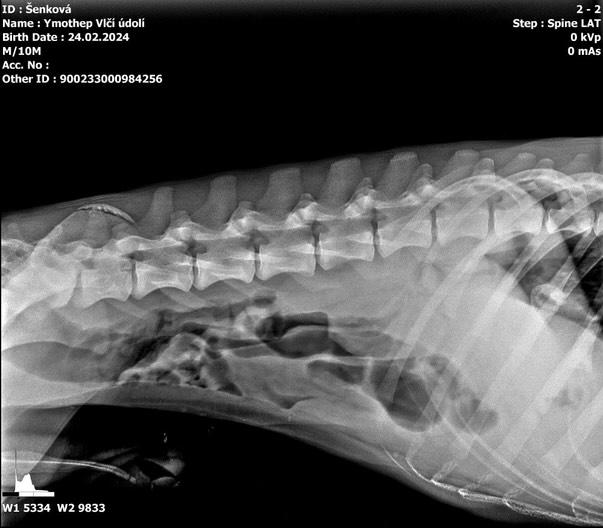

DOB: 02/24/24